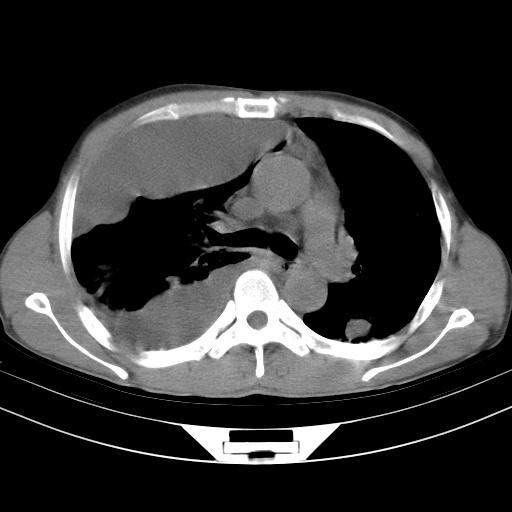

男性,44岁,结核病史多年。现胸闷气短,咳嗽,偶咳血。

右侧胸腔积液

右肺下叶不张

双肺多发结节影最分空洞形成考虑占位不除外结核

1、右侧大量胸腔积液伴右肺压缩性膨胀不全,建议抽液治疗后复查 2、两肺继发性tb伴空洞形成。

1)两肺继发性肺结核伴空洞形成,左肺多发性结核球。2)右侧大量胸腔积液伴右肺部分膨胀不全。3)纵隔淋巴结肿大。